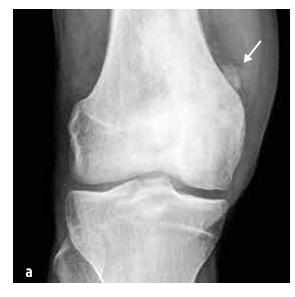

Examenul de bază este radiografia nativă a zonelor simptomatice (vezi imaginea nr. 3), completată cu examinare prin rezonanță magnetică și/sau tomografie computerizată.

Imaginea nr. 3

Extinderea și leziunile osteolitice ale capătului medial al claviculei stângi și edemul țesuturilor moi pe radiografie